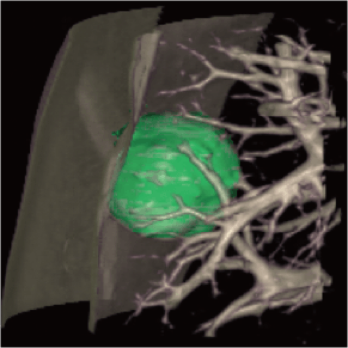

3 core components built on a new industry-leading configuration

Large-capacity tube delivers exceptional stability and durability, ensuring consistently high-quality output even under heavy workloads

High-power generator delivers high mA output for rapid scanning of complex anatomy and large coverage areas, boosting scan speed while enhancing image signal-to-noise ratio and minimizing artifacts

Wide detector expands single-rotation coverage, shortens exam time, reduces motion artifacts, decreases radiation dose, and saves tube exposure time while effectively lowering operating costs